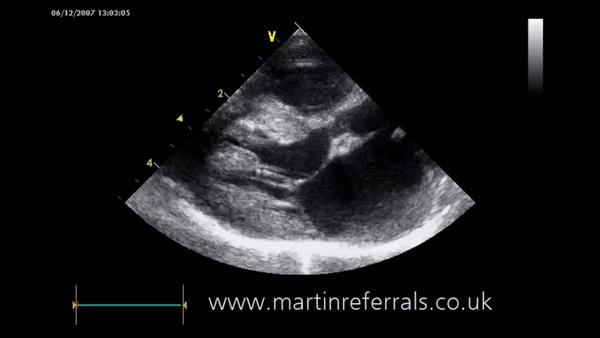

● 患猫们的临床症状和超声心动图没有特异性差异;

TMT和HCM小猫的重要指标 感兴趣可以点开大图看 图自:引文[1]

超声心动图图自:martinreferrals.co.uk